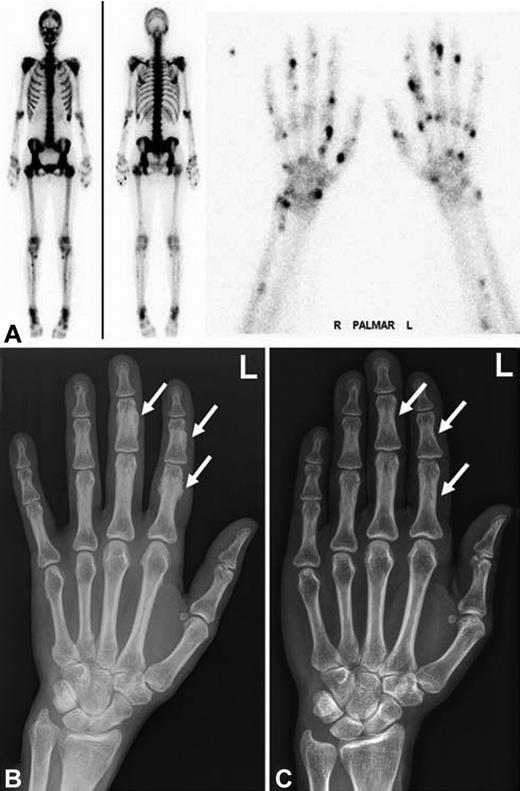

Radiographic findings and bone scintigraphy in patient 1. (A) Technetium 99m-methyl-diphosphonate bone scintigraphy showing marked tracer uptake in the entire skeleton, most pronounced in the spine and pelvis (left). There are multiple active spots in bones of both hands (right). (B) Plain film showing marked periosteal bone apposition on diaphysis of the phalanges of the left hand (arrows). Findings are typical for hypertrophic osteoarthropathy. The image was taken after 9 months of voriconazole therapy. (C) Plain film showing resolution of periosteal bone appositions on diaphysis of the phalanges (arrows). The image was taken 5 years after cessation of voriconazole therapy.

We report 3 patients on long-term voriconazole treatment who developed clinically significant skeletal disease, which was completely reversible after termination of voriconazole (Table 1). All 3 patients were female allogeneic stem cell transplant recipients with cyclosporine-related moderate chronic renal failure. Disseminated bone pain started between 3 and 7.5 months of voriconazole treatment. Laboratory findings included an elevated alkaline phosphatase and bone-specific alkaline phosphatase, normal levels of calcium, phosphate, parathyroid hormone, 25-hydroxyvitamin D, and a slightly elevated urinary deoxypyridinoline/creatinine quotient. Conventional radiographs, CT scans, and bone scintigraphy revealed periosteal appositions and focal tracer uptake, respectively (Figures 1 and 2). CT scans of the chest and abdomen showed no signs of secondary malignancies, and bone marrow biopsies ruled out recurrence of the acute leukemia. Patients 1 and 2 were initially misdiagnosed as having an unusual musculoskeletal presentation of GVHD; hence, the immunosuppression was intensified. However, the pain was only temporarily attenuated by corticosteroids and methotrexate but disappeared almost completely in all 3 patients within 4 days of voriconazole cessation. The diagnosis of voriconazole-induced skeletal disease was made only retrospectively in patient 1, 20 months after occurrence of the first symptoms in patient 2, and without delay in patient 3. Serum fluoride measurements at diagnosis were available for patients 2 and 3 with > 10-fold elevated levels and a marked decrease within 3 weeks of voriconazole cessation (81% and 57% of precessation values, respectively). Long-term follow up of 5.5 years after the initial diagnosis revealed complete resolution of the skeletal changes in patient 1 (Figure 1).